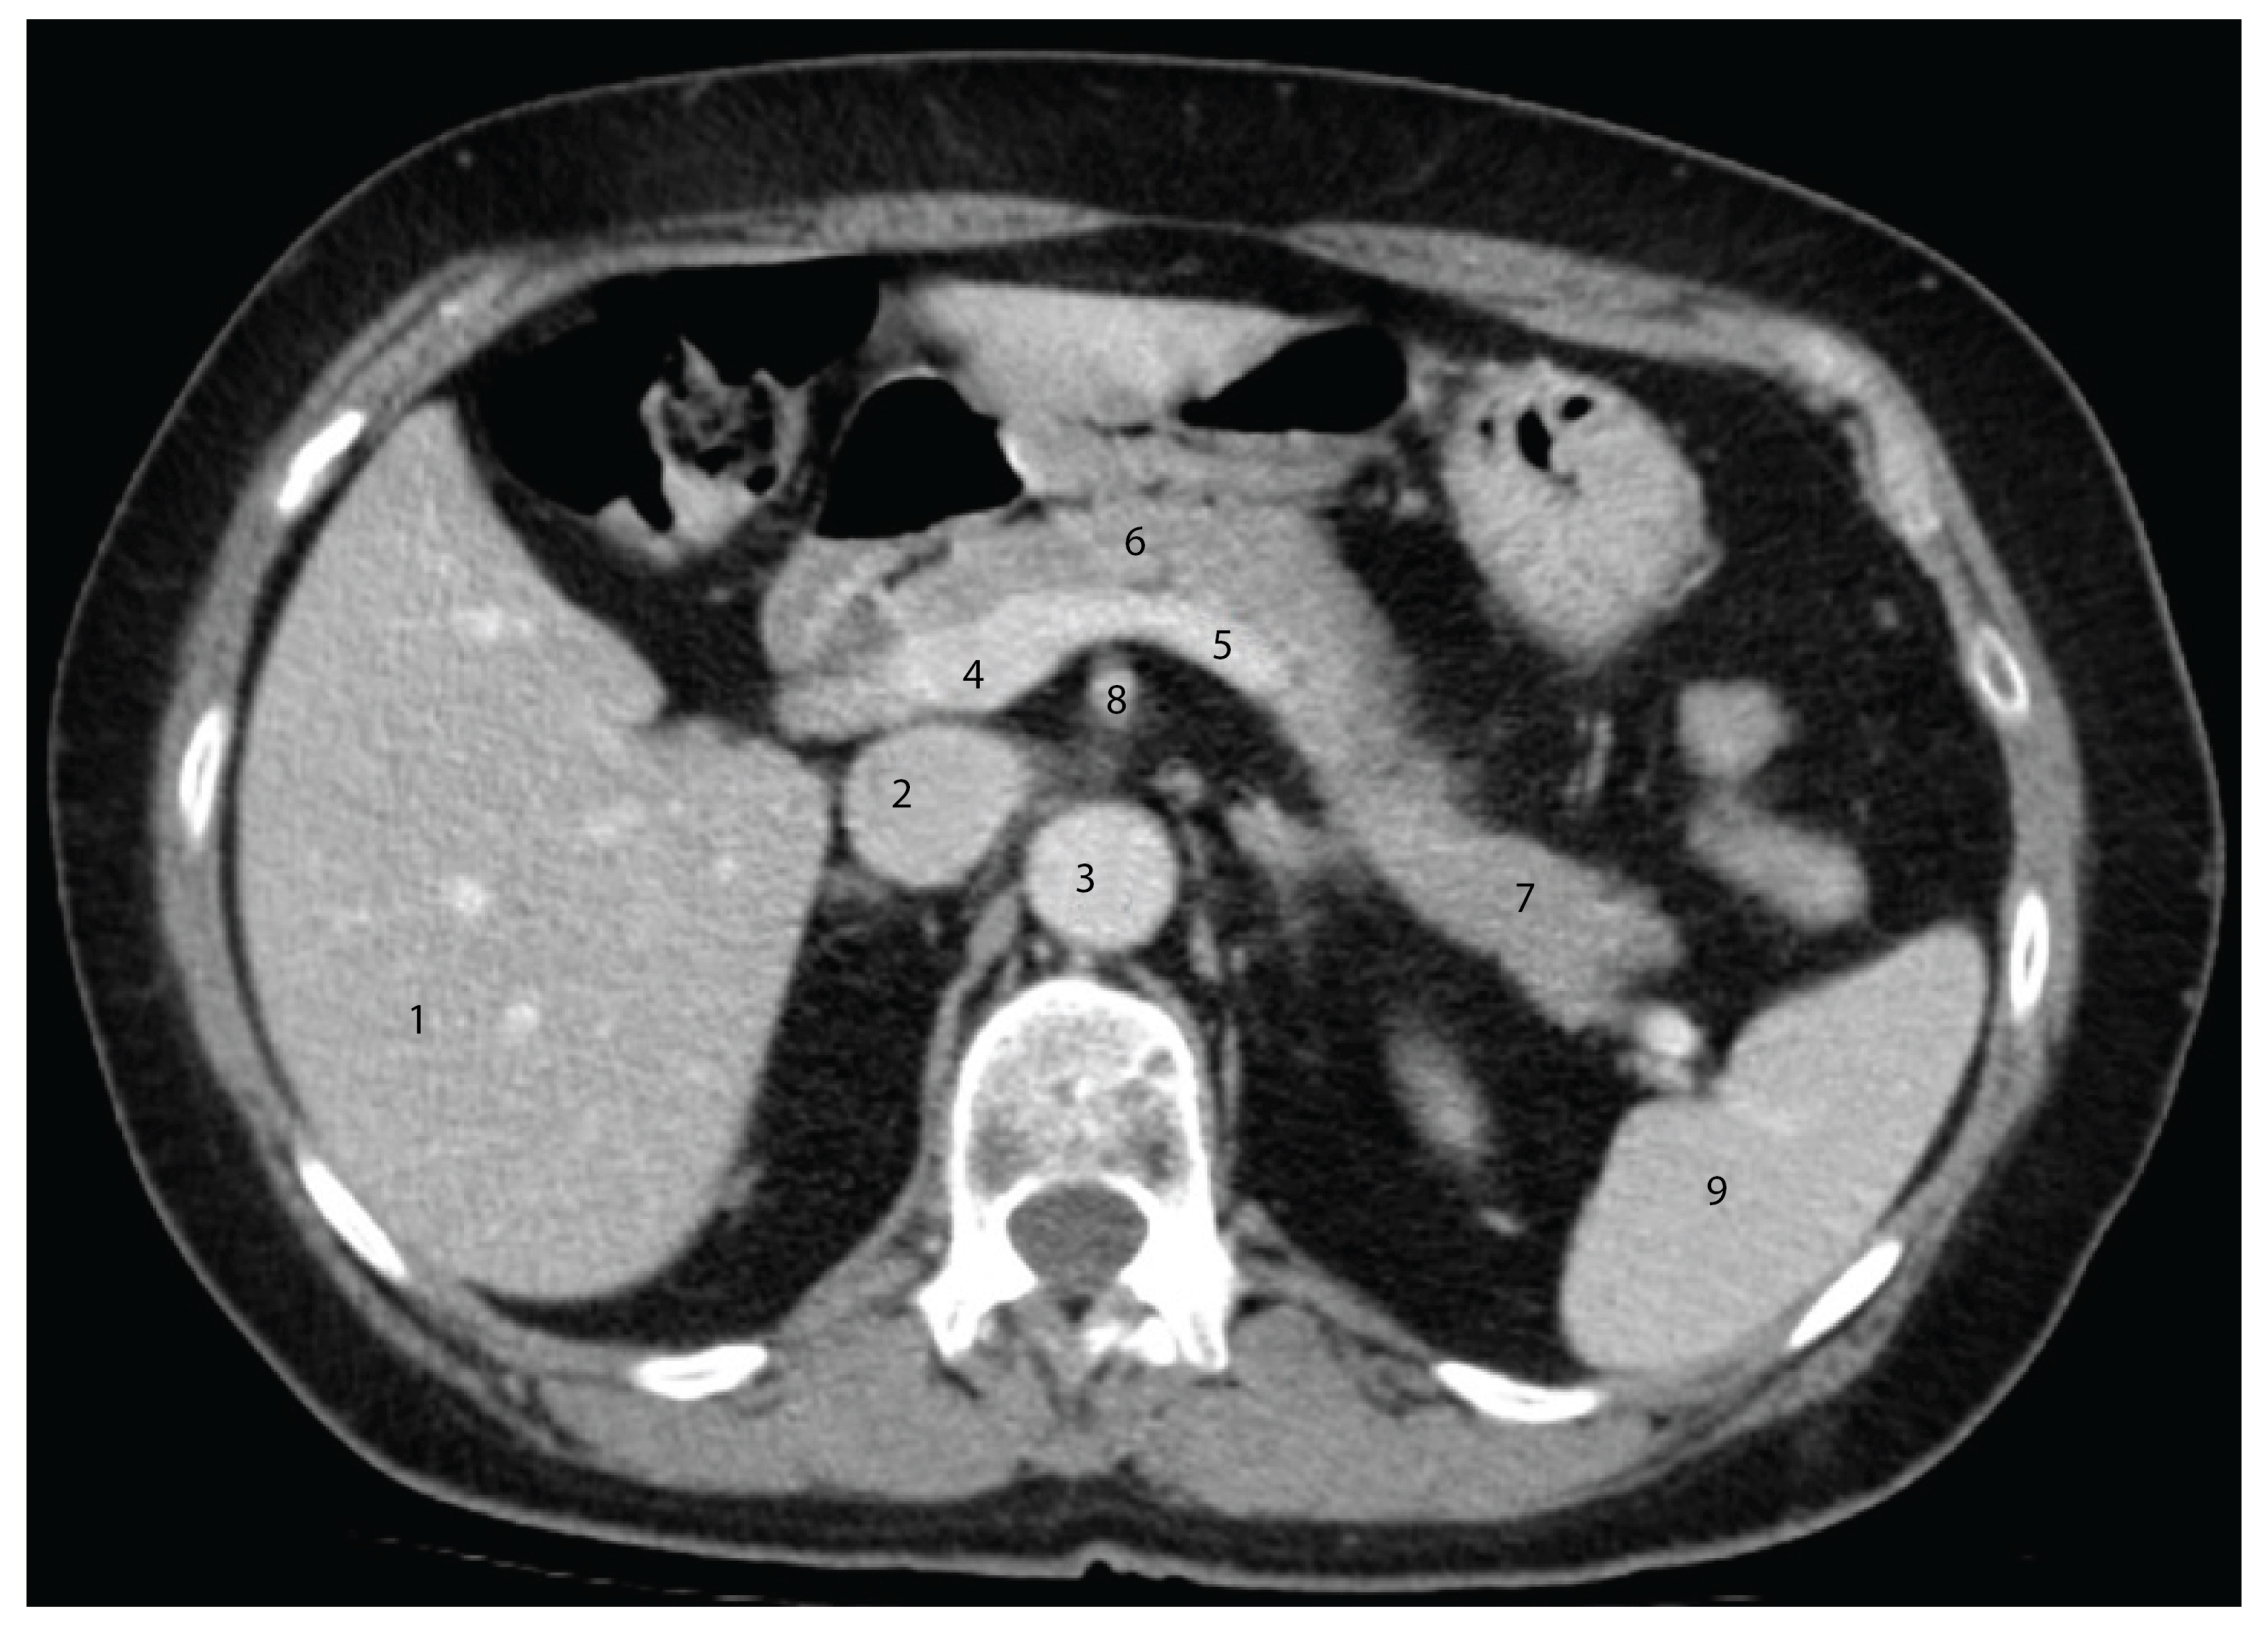

4.5. Advances in Imaging